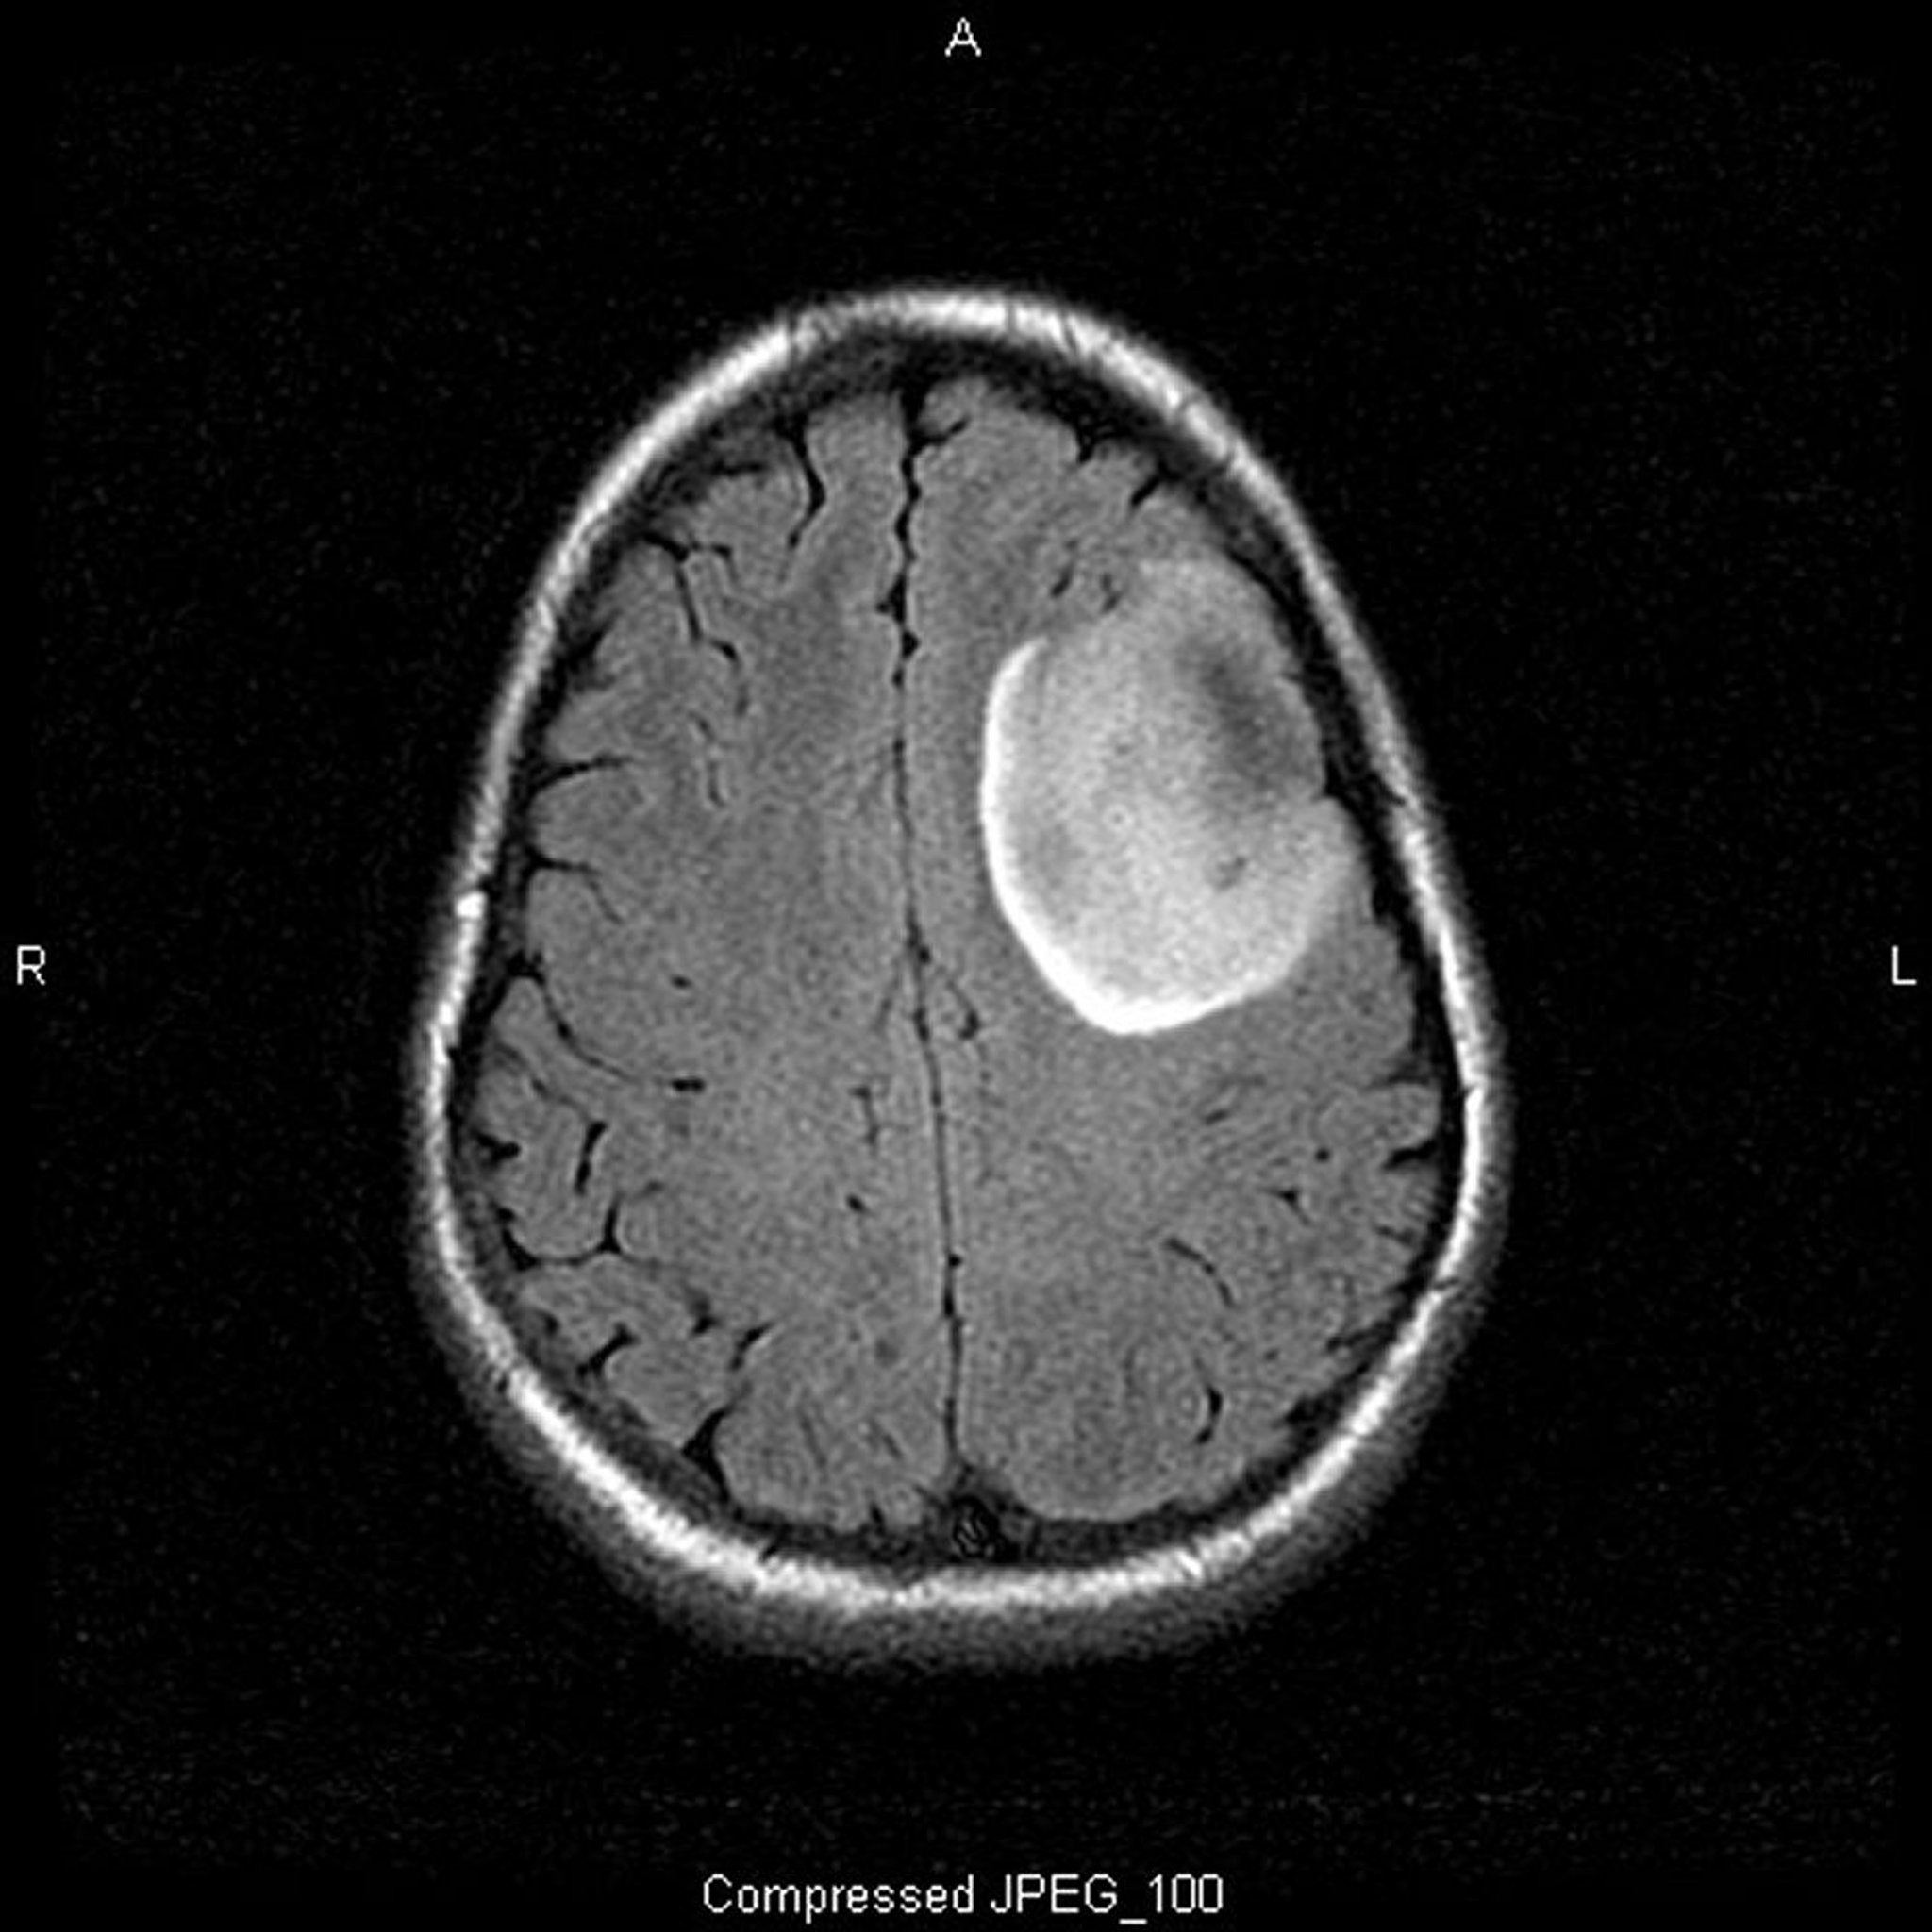

Oligodendroglioma de baixo grau

Essa RM ponderada em T2-FLAIR (fluid-attenuating inversion recovery, recuperação de inversão atenuada por fluidos:) mostra um sinal branco, que pode indicar uma massa ou edema. O sinal frontal esquerdo está bem demarcado, sugerindo massa. O uso de contraste não o realça. É um oligodendroglioma de baixo grau (grau II).

Imagem cedida por cortesia de William R. Shapiro, MD.